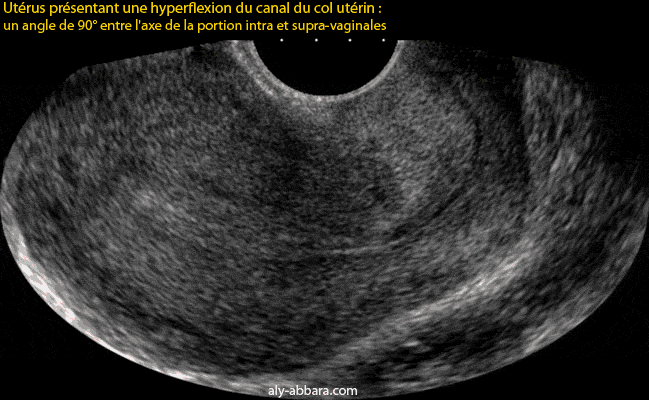

Utérus antéfléchi, antéversé avec une hyperflexion du canal cervical

• L'angle formé par les axes des deux portions du canal cervical, c'est-à-dire la portion intra-vaginale et supra-vaginale est habituellement proche de 180° et dans le cas présent, on remarque la présence d'une hyperflexion de ce canal avec un angle proche de 90°.